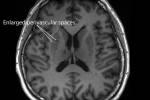

وقام الباحثون بتحليل صور الأشعة المقطعية للدماغ واختبارات الحالة العقلية المصغر لإجمالي 332 شخصاً، في مراحل مختلفة من المرض.

وفي الرجال، كان هناك ⁠انكماش أكبر بالمادة الرمادية في ‌الدماغ خلال المراحل المبكرة من ‌المرض، مع درجة معينة ​من الاستقرار بعد ذلك، ‌أما في النساء فقد كان انكماش المادة ‌الرمادية بطيئاً في المراحل المبكرة من المرض ليصبح أكثر حدة وانتشاراً في المراحل المتأخرة من التدهور الإدراكي.

وتشير نتائج درجات اختبارات الحالة العقلية المصغر الطبيعية لدى النساء ‌اللاتي يعانين تقلصاً مبكراً في المادة الرمادية إلى أن أدمغتهن، ربما ⁠تعوض ⁠ذلك بطرق تساعد في الحفاظ على الأداء الإدراكي في المراحل المبكرة من المرض.